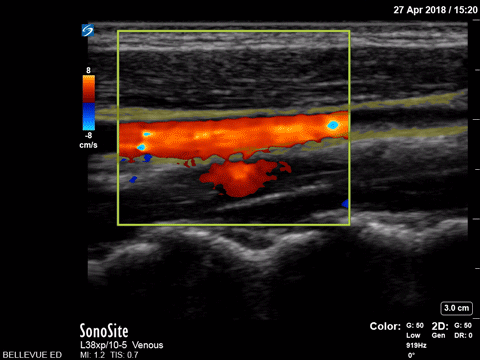

Long Axis Doppler of Common Carotid Artery and Internal Jugular Vein Yellow outline: Internal jugular vein, Green outline: Common carotid artery Images: Dr. Lindsay Davis, Dr. Hannah Kopinski. Image Editing: Michael Amador and Dr. Matthew Riscinti